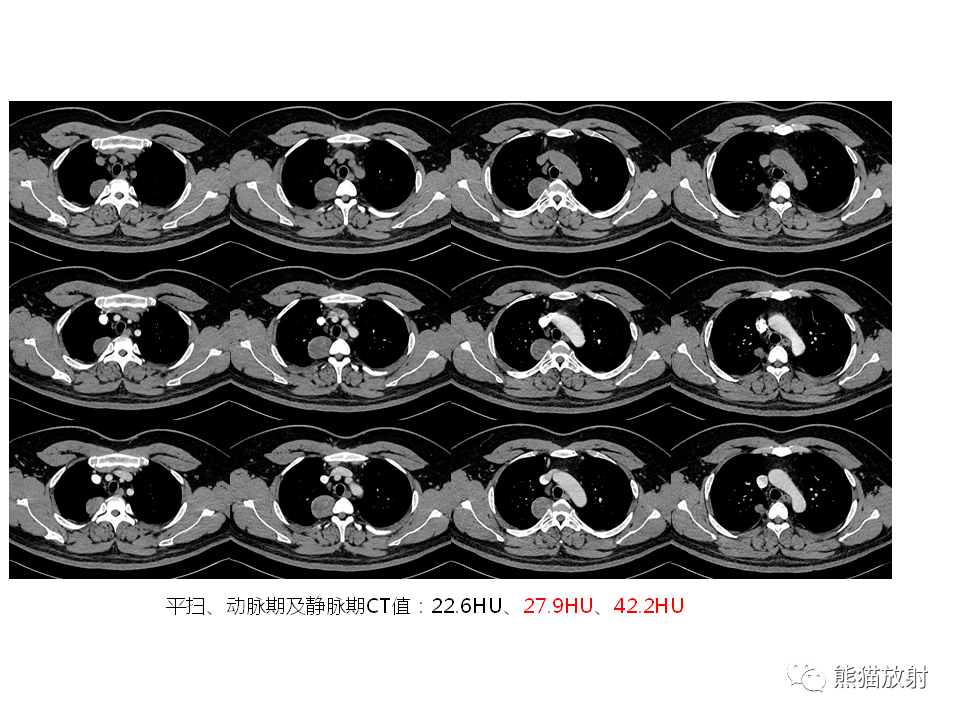

后纵隔脊柱旁占位,囊肿?还是囊性改变?请赏析!

图片尺寸1098x1010